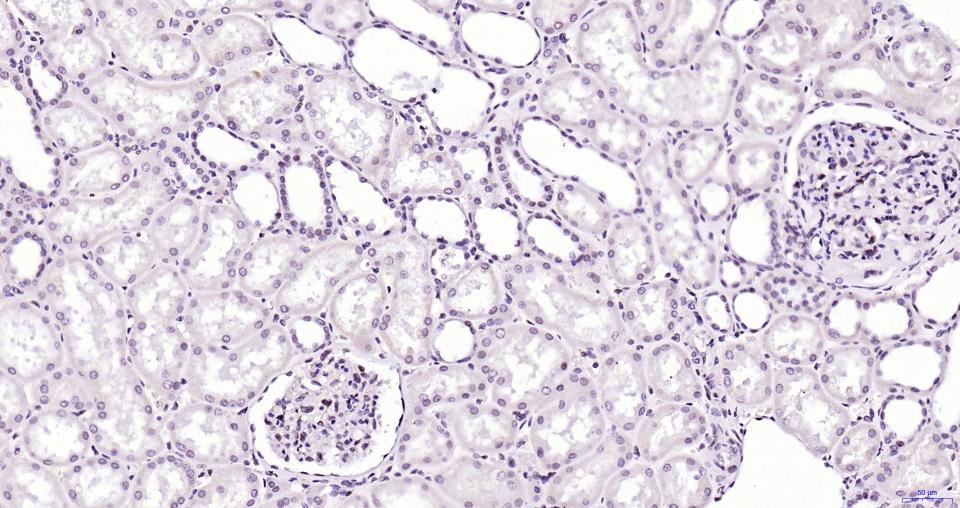

Paraformaldehyde-fixed, paraffin embedded Mouse Kidney; Antigen retrieval by boiling in sodium citrate buffer (pH6.0) for 15 min; Antibody incubation with BRD4 Monoclonal Antibody, Unconjugated(bsm-61190R) at 1:200 overnight at 4°C, followed by conjugation to the bs-0295G-HRP and DAB (C-0010) staining.